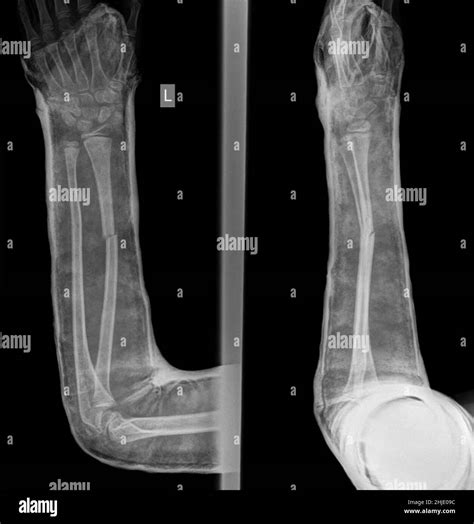

Fractured Hand Xray

Injuries to the hand are common and can range from minor cuts and bruises to more severe fractures. One of the most critical diagnostic tools for assessing hand injuries is the Fractured Hand Xray. This imaging technique provides detailed images of the bones in the hand, helping healthcare professionals to accurately diagnose and treat fractures. Understanding the process, importance, and interpretation of a Fractured Hand Xray is essential for both medical professionals and patients.

Interpreting a Fractured Hand Xray

Interpreting a Fractured Hand Xray requires specialized knowledge and training. Radiologists and orthopedic surgeons are trained to identify various types of fractures and other abnormalities in the hand. Here are some key points to consider when interpreting a Fractured Hand Xray:

• Bone Alignment: Check for any misalignment or displacement of the bones.

• Fracture Patterns: Identify the type of fracture, such as transverse, oblique, or comminuted.

• Soft Tissue Involvement: Look for any signs of soft tissue damage or swelling.

• Joint Involvement: Assess whether the fracture extends into the joints, which can affect treatment and recovery.

Radiologists use these observations to provide a detailed report that guides the treatment plan.